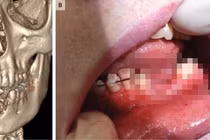

Tuần trước, 14 tiểu bang ở Mỹ cũng đã báo cáo gần 100 trường hợp bệnh phổi bí ẩn liên quan đến thuốc lá điện tử. Các bệnh nhân, trong đó có cả thanh thiếu niên, nhập viện với triệu chứng khó thở và đau tức ngực.

Một số còn bị sốt, ho, nôn và tiêu chảy. Ban đầu, các bác sĩ nghĩ rằng đó chỉ là các triệu chứng nhẹ của bệnh truyền nhiễm do virus hoặc viêm phổi do vi khuẩn. Tuy nhiên, biện pháp điều trị thông thường như kháng sinh đã không có tác dụng.

Bệnh tình của các bệnh nhân tiếp tục xấu đi, một số người suy hô hấp đến mức độ phải đặt máy thở. Cá biệt, một trường hợp bệnh nhân tử vong đã được báo cáo.